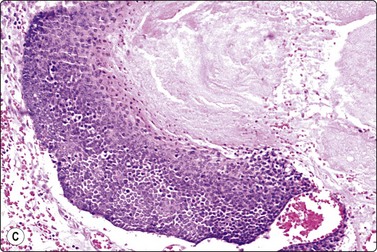

image image image

Fig. 14.10 Syringocystadenoma papilliferum

Clustered and dispersed epithelial cells; moderate amount of cytoplasm; mildly atypical nuclei; no true papillary fragments (A, MGG, HP; B, H&E, IP); (C) Corresponding tissue section (H&E, LP).

Benign skin adnexal tumors located to the breast or axilla can be mistaken for primary or metastatic breast cancer.33,35 Knowledge of the exact localization of the lesion and its relation to the skin is essential when examining FNBs, as illustrated by the following case from our files:

A 60-year-old woman with a history of right mastectomy for cancer 4 years previously presented with a lump in the right axilla. It was described as subcutaneous by the surgeon who performed the FNB and the clinical diagnosis was metastasis of breast cancer. Smears were highly cellular, of epithelial cells both forming cohesive aggregates and dispersed as single cells. True papillary fragments were not seen. The cells had a moderate amount of dense cytoplasm and there was relatively mild nuclear atypia (Fig. 14.10). The pattern was considered to be in keeping with metastasis of a low-grade breast carcinoma. However, the nodule was, in fact, intracutaneous and the histology was reported as syringocystadenoma papilliferum (Fig. 14.10).36